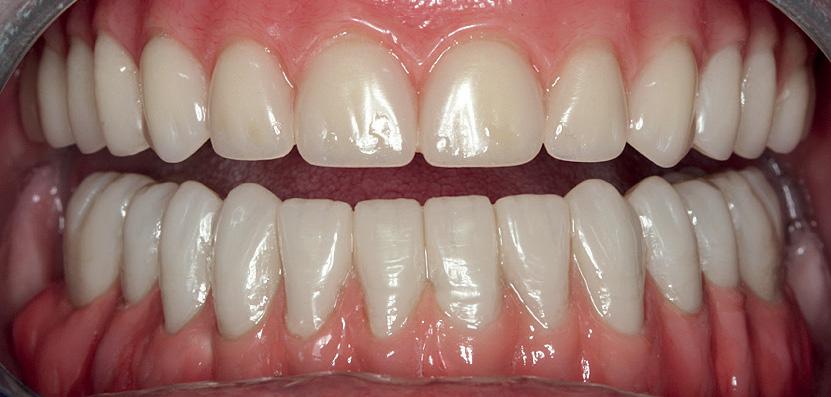

A 23-year-old girl presented to the oral and maxillofacial clinic referred by her general dental practitioner as an emergency. She had history of recurrent pain and discomfort associated with her lower wisdom teeth. The dentist attempted to remove her lower right wisdom tooth (RL8) under local anaesthetic to alleviate pain but was not able to anaesthetise and decided to refer her to a maxillofacial surgeon.

She was fit and well and a regular visitor to her dentist. During the consultation visit, the patient described having pain on the right lower side. Clinical examination revealed that RL8 was partially erupted showing mild pericoronitis with soft tissue lacerations, suggesting a recent attempted extraction. LL8 was impacted, UR8 was buccally inclined and UL8 partially erupted and buccally inclined and traumatising cheek mucosa.